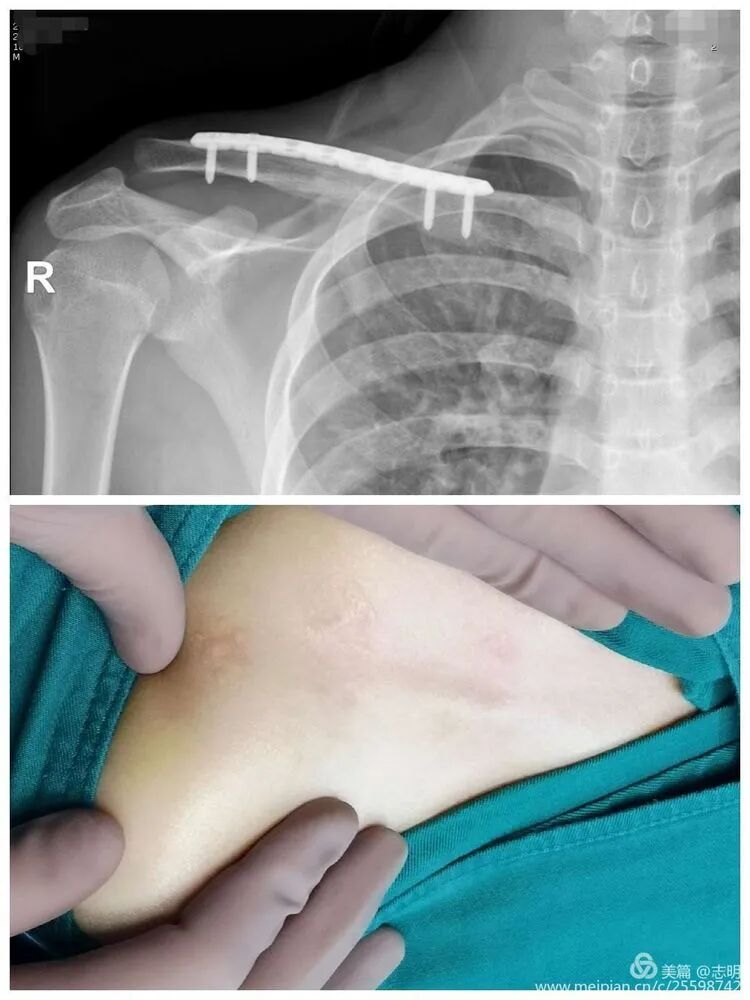

(Example of pre-operative imaging, likely an X-ray showing fracture).

(Image showing patient preparation with clavicle marked and padding).

(Image showing the sterile draping including the arm).